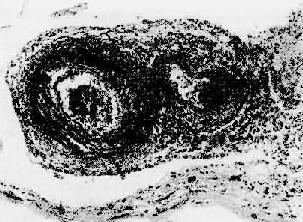

狼疮性肾小球肾炎

图4-10 狼疮性肾小球肾炎

肾小球毛细血管丛节段性纤维素样坏死,伴系膜细胞增生;间质炎细胞浸润